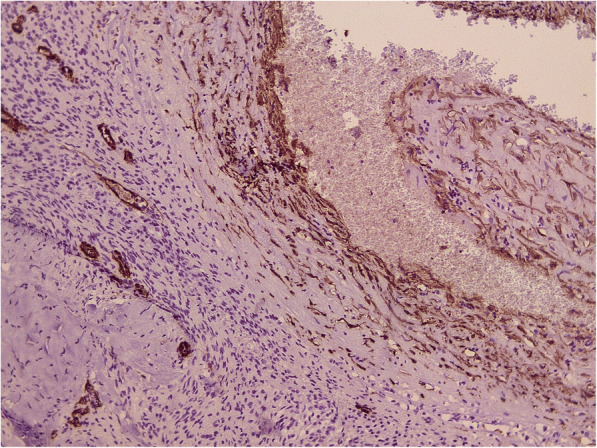

Fig. 3.

Cavernous malformation was confirmed by SMA. Another part of the tumor (× 100)